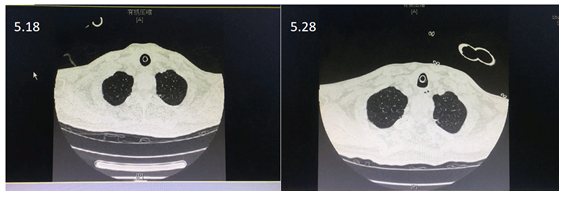

入院时经口气管插管,呼吸机辅助通气,模式SPONT,PS 12 cmH2O,PEEP 5 cmH2O,FiO2 0.3,气道内可吸引出大量黄色Ⅱ度黏痰,意识清楚,精神差。T 36.5℃,P 78次/min,R 18次/min,SpO2 98%,BP 108/62 mmHg。双下肺呼吸音低。胸部CT示双下肺肺不张,右侧包裹性胸腔积液。

患者感染学指标均基本正常(图1);两下肺存在肺不张,右侧包裹性胸腔积液(图2);呼吸力学指标正常(图3)。纤支镜下可见痰液较多,呈黄色,Ⅱ度黏痰(图4)。

图2 患者胸部CT

气道管理效果较为明显,5月28日,患者双下肺肺不张明显改善,且在未使用抗生素的情况下,患者未发生感染(图8)。

图8 患者治疗前后胸部CT对比